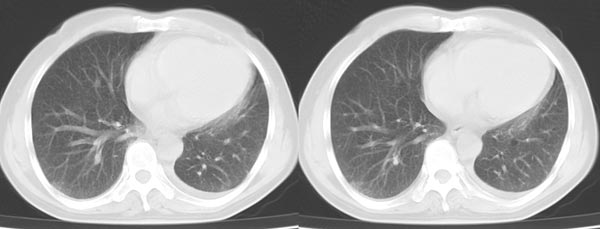

以下是引用dyqct在2006-4-1 22:20:00的发言:[br]左肺上叶明显萎陷、实变,支气管大部通畅,部分扩张,部分壁似见串珠状钙化。主动脉弓旁见肿大淋巴结。纵隔左移。左侧胸壁后缘见新月形高密度,边界清楚。[br] 考虑:1、左肺上叶肺不张伴支气管扩张(牵拉性),可能为支气管内膜结核所致。[br] 2、左侧少量胸腔积液。[br]

以下是引用piao001在2006-4-2 14:13:00的发言:[br]左肺上叶不全性不张,其内见钙化及扩张支气管,结合病史,考虑支气管内膜结核。建议支气管镜明确检查。